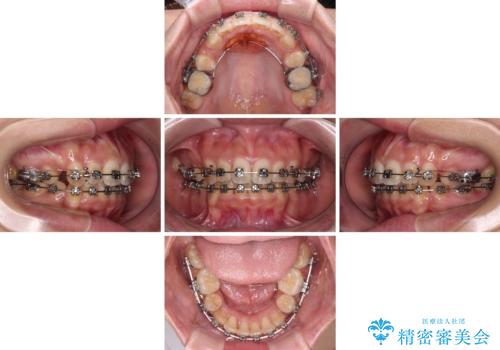

- メタルブラケット

- 3年3ヶ月

- 30回以上

奥歯の噛み合わせは正常に近い状態でしたが、右上の奥歯に突起があったり、上下前歯が非接触であったりしていたため、補助装置を使用して上顎前歯を積極的に引っ込めるように計画しました。

口元の突出感を改善するために上下左右の小臼歯4本を抜歯し、ワイヤー装置によりデコボコを解消しながら口元の突出感も改善していくこととしました。

上下の前歯が接触する仕上がりとなったので、横顔の印象が大幅に改善されました。